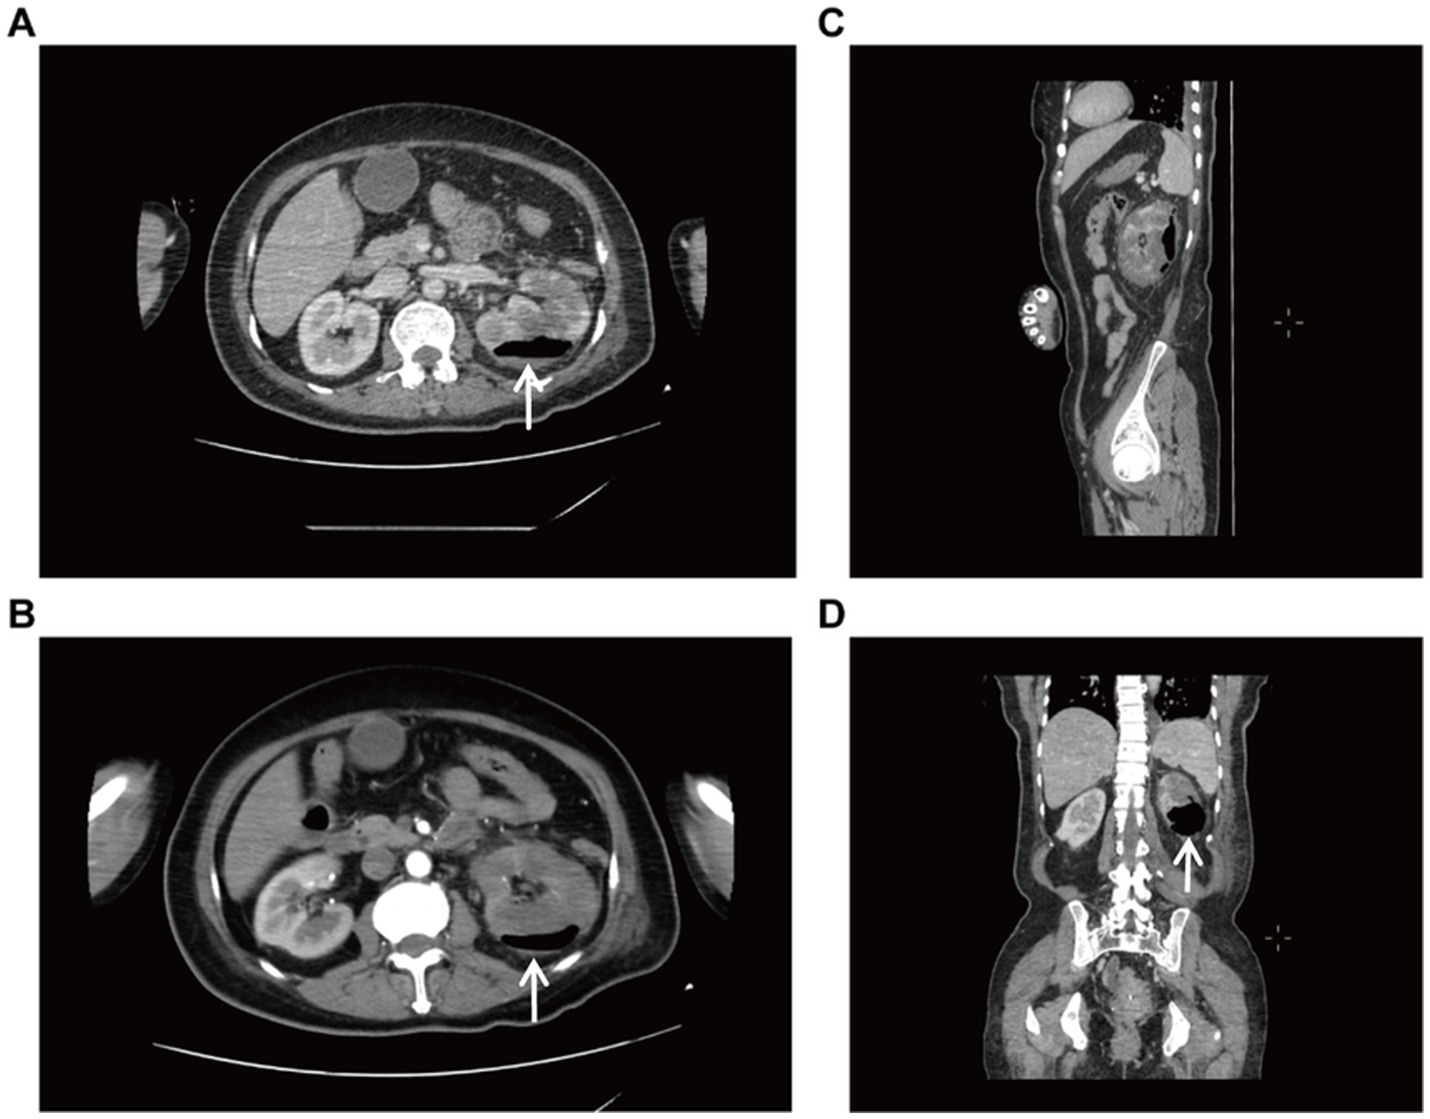

A 56-year-old female patient presented to our hospital on January 28, 2025 with left lower abdominal pain for 5 days. She had a history of diabetes mellitus for more than 10 years, and had been taking metformin and subcutaneous insulin injection at bedtime for a long time to control her blood glucose, with a fasting blood glucose of about 11 mmol/L. The patient occurred left lower abdominal pain with intermittent vomiting without obvious triggers, no chills and high fever, no hematuria and urinary tract irritation 5 days before admission. And she was admitted to an outside hospital for CT scanning of the whole abdomen: the left kidney low density foci with gas density shadow, the left pelvis and calyces of the left kidney and the left ureter intermittent dilatation,suggesting emphysematous pyelonephritis (EPN) and perirenal infection. She received empirical antibiotics (cefoperazone and moxifloxacin) with poor response. Upon admission to our hospital, physical examination demonstrated percussion pain in the left renal region and ureteral point tenderness. Contrast-enhanced abdominal CT showed an enlarged left kidney with patchy hypodense areas and intraparenchymal gas (Figure 1), with the largest gas collection measuring 51 × 42 × 15 mm in orthogonal diameters on venous-phase images, along with perirenal exudation, consistent with EPN. Laboratory examination on admission: WBC 8.03 × 109/L, neutrophil 6.59 × 109/L, PLT34 × 109/L, ultrasensitive CRP 281.68 mg/L, procalcitonin 30.4 ng/mL, fasting blood glucose 12.2 mmol/L, SCr130.1 μmol/L. Urine routine: urine RBC 3+, urine protein 2+, urine glucose 4+, leukocyte esterase 1+. Diagnosis: 1. Acute emphysematous pyelonephritis (left), 2. diabetes mellitus.

Figure 1. Enhanced CT of the whole abdomen. (A) Transverse view (venous phase), increased volume of the left kidney with internal gas shadows. (B) Transverse view (arterial phase), showing a patchy hypodense shadow and gas accumulation of the left kidney. (C) Sagittal view. (D) Coronal view, massive emphysema.